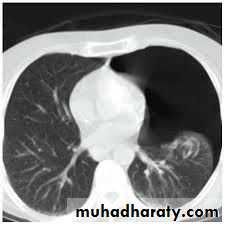

Area of hypertranslucensy (pneumothorax)

What is the difference?

(emphysematous bullae) (pneumothorax)